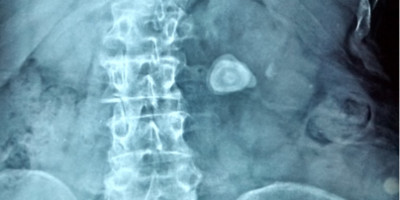

How Is The Diagnosis Confirmed?

• Ultrasound scan, CT scan and x-rays are usually adequate to confirm the presence of stone, it's location and size and severity of obstruction.